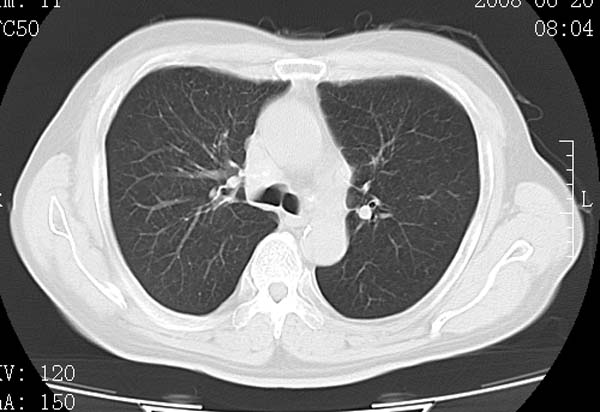

以下是引用守望可可西里在2008-6-24 1:11:00的发言:[br][br] 考虑为周围型肺癌:[br] 1.分叶结节,形态极不规则,蟹足样伸展的恶性浸润特征比较明确。[br] 2.磨玻璃影中由多个更高密度小结节聚集呈梅花瓣样。[br] 3.局部胸膜凹陷征比较明确。[br][br] 另:纵隔胸膜明显增厚、粘连。

以下是引用zjzjr在2008-6-24 11:19:00的发言:[br]支持左下肺周围型肺癌伴右肺转移,纵隔淋巴结转移,心包积液.

以下是引用zhangling在2008-6-24 14:56:00的发言:[br]我们科室意见报告为[br][br]1考虑左下肺周围型肺癌[br]2右肺小结节考虑转移瘤,纵隔淋巴结转移[br]3心包积液. [br] 各位老师分析的相当好 谢意[br]